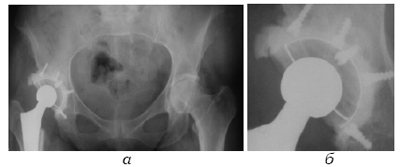

Вышеуказанная техническая погрешность приводит: во-первых, к перелому неравномерной цементной мантии (прокладки) в ее тонкой части (Haas S.S. et al., 1975; Judet T., 1997; Courpied J.P.,

1998)(рис. 2б), что приводит к нестабильности, во-вторых, в зоне контакта импланта (полиэтилен или металл) может наблюдаться остеолиз (Pazzalgia U.E. et al., 1985; Barrack R.L. et al., 1997; Nizegorodcew T., Gasparini G. et al., 1997), что опять же приводит к расшатыванию, и в-третьих, к неправильным углам установки кубка (Judet T., 1997; Sanchez-Sotelo J., 2002), что чревато вывихами, ограничением движений и даже расшатыванием кубка, вследствие действия неправильных биомеханических сил.

Рис. 2. Пример использования ацетабулярного кубка без цементных спейсеров: а. рентгенограмма эндопротеза левого ТБС, б. тот же снимок в увеличении -неравномерное распределение цементной мантии (стрелкой указана зона перелома «тонкого цемента»)